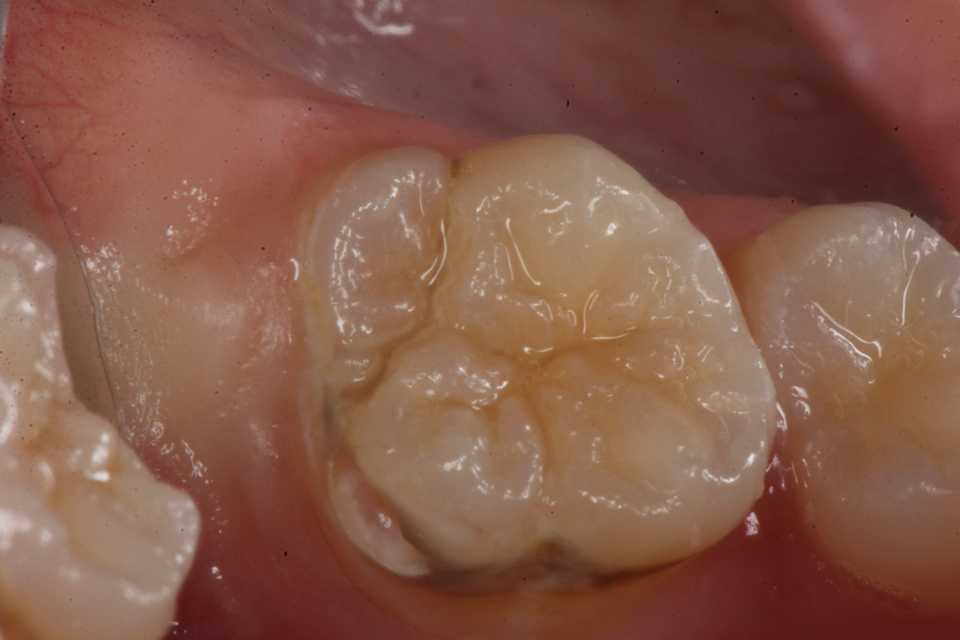

50代女性、左上7、外傷性近心辺縁隆線破折、クラック、自覚症状なし食いしばりの癖がある方で、手前側の6番も補強冠を入れて歯牙破折をなんとか抑えている。この7番も割れて抜歯になる前に補強冠を装着するしかないだろう。とりあえず今日は既存のアマルガムを除去しCRで修復するまで。では時系列でどうぞアマルガムにもクラック(ヒビ)が入っている。クラックα-TCP手前は補強冠、後ろの7番も同じようにするしかないだろう。クラックが深部に進んで離断してしまったら抜歯になる。つづく